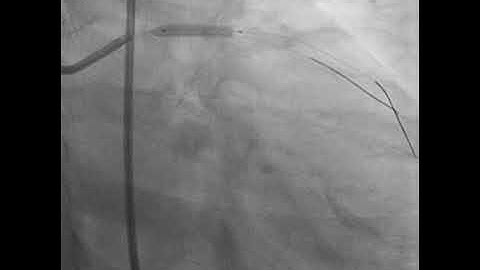

Coronary bifurcation stenting: modern algorithms and details of provisional techniques- Elias Hanna